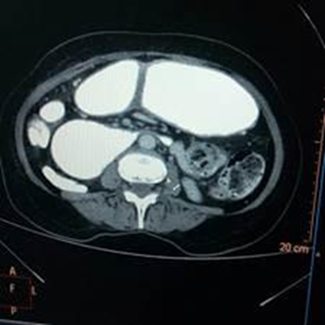

Tac de abdomen y pelvis (figura 2) se encuentra pinzamiento aortomesentérico en segunda porción del duodeno compatible con Síndrome de Wilkkie, descartando de esta forma el diagnostico presuntivo de masa que antes se había considerado.

Figura 2. Tac de abdomen y pelvis